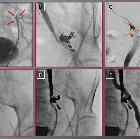

graft for arterial injury management: safety, technical success, and long-term outcome. Viabahn stent graft for endovascular treatment of uretero-iliacal fistula. In an 80-year-old male patient with a complex medical history, including extensive prior surgery and chemotherapy for colon carcinoma, multiple prior surgeries for urolithiasis, and ureteric stent implantation, the removal of the ureteric stent led to massive hematuria. A Subsequent ureterorenoscopy revealed the presence of a fistulous connection between the left ureter and the adjacent left internal iliac artery (red arrows), B which was first addressed through coiling. C Due to residual perfusion (orange arrows), D a Viabahn stent graft was deployed. E Ureterography showed no remaining perfusion of the fistula. F Final target site angiography demonstrated preserved left iliac blood flow